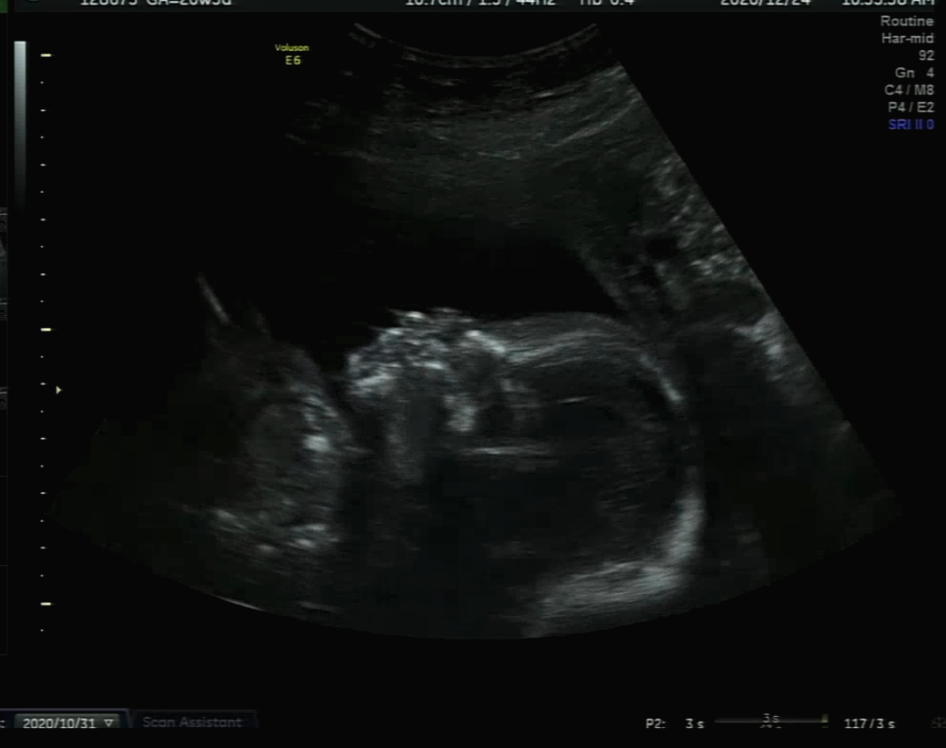

아내의 임신

지난 9월 아내가 임신했다는 사실을 알게되었다. 임신을 계획하고 있었지만 막상 현실이 되고나니 비현실적이기도하고 무섭기도했다. 산부인과에서 임신진단을 받고나서야 '정말 아이가 생겼구나' 정도의 생각이 들었다. 그리고 머지 않아 초음파를 통해 아이의 형태를 볼 수 있게 되자 그때부터는 새로운 생명이자 우리의 아이가 자라고 있다는 것이 내 마음에 각인되었다. 아이의 실체가 와닿은 것이다. 몇 주 되지도 않은 그 조그마한 생명체가 움직이는 모습을 볼때마다 모니터로 빨려들어갈 것 같았다. 이제 임신 6개월차에 접어든 아내의 배는 제법 나왔고 종종 태동이 배에서 내 손으로 느껴지기도 한다. 올해 5월이면 녀석을 만나게 될 것이다. 아기의 시간은 잠깐이고 한 명의 사람이 되어갈 아이에게 좋은 아빠가 되어주고 싶다.